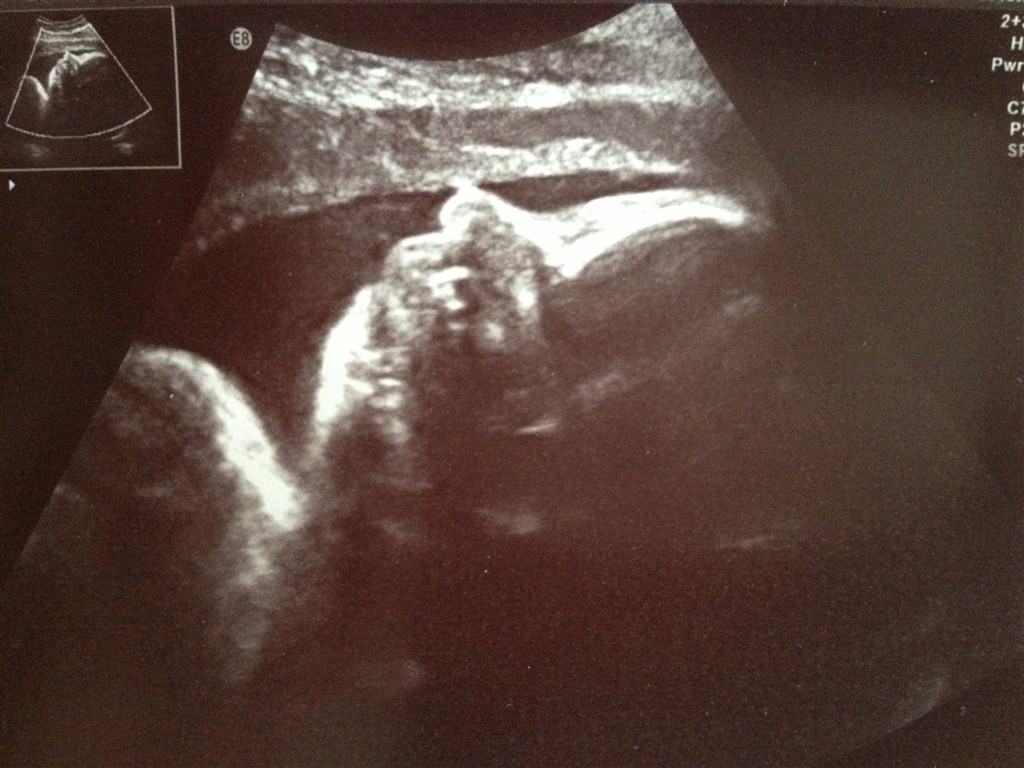

Vi fik også taget et par billeder af pigerne. Baby A ville gerne vise sig frem

Det ville Baby B dog ikke. Hun blev ved med at gemme sig bag armen, så vi fik et billede af hendes fod i stedet for